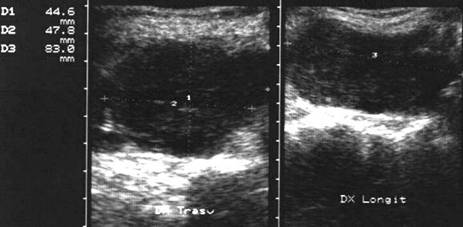

Carcinom ANAlaZic.Recidiva laterocervicalA

Femeie de 73 ani. Recidiva laterocervicala dreapta

dupa meta de carcinom anaplazic.

Prima imagine este efetuata la 3 luni dupa interventia chirurgicala si evidentiaza

o leziune de 20x23x24mm (5,7 cc).

A doua imagine s-a efectuat la 25 de zile dupa prima; leziunea masoara 33x42x40mm,

(29 cc).

Examen citologic: carcinom anaplazic.

Aceeasi pacienta - vascularizatie slaba la doppler datorata necrozei.